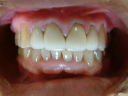

初診と最終補綴物

患者さんにも満足して頂けた最終補綴物 |

患者さんは、自分のイメージした補綴物

が出来上がってくるか不安だと思いますが

テックで歯の長さや、形態を確認することで

信頼関係が出来上がるようです。 |